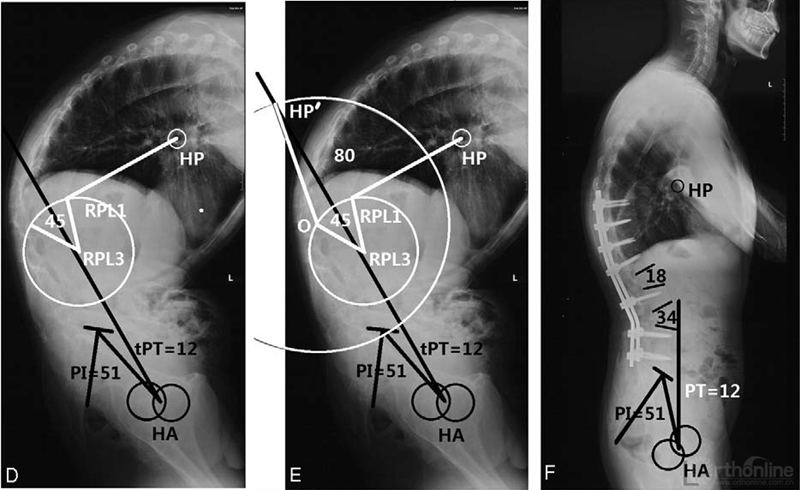

骶骨倾斜角(sacral slope, SS)反映骶骨倾斜的程度,SS值随着AS矢状面畸形的发展而不断变化,当后凸不断发展,势必导致人体重力线落于股骨头和骶骨前方造成矢状位失衡,人体为代偿这种变化迫使骨盆围绕股骨头向后方旋转使重力线重新落回股骨头和骶骨上,这种代偿变化造成了骶骨向后倾斜,SS值变小甚至为负值。一篇研究报道了SS负值预示着矢状位失衡的严重和代偿的增大,并且SS值也与许多反应后凸畸形角度的参数明显相关。

图10 骶骨倾斜角负值患者与骶骨倾斜角正值患者的矢状位对比

(图片资料摘自Qian等The Presence of a Negative Sacral Slope in Patients with Ankylosing Spondylitis with Severe Thoracolumbar Kyphosis, J Bone Joint Surg Am, 2014, 96(22):e188.)